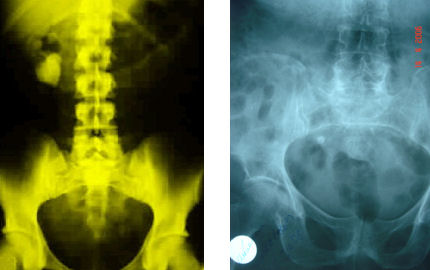

Radiology :

For every patient referred for stone or similar complaints, direct urinary system radiography (DUS) should be taken after the urine test and a complete abdominal ultrasonography (US) should be applied by considering the differential diagnosis.

As we specified above, 85% of the stones include Ca, therefore they may be seen in direct radiographies. US should also be taken to see whether a dilatation is present in the kidney.

If a final diagnosis can not be established by these two tests; Uropgraphy (IVP) taken by administrating colored agents intravenously or Computed Tomography (CT) with or without intravenous colored agent may be utilized.